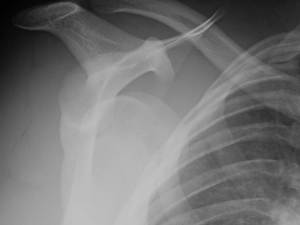

Reducing a Shoulder

anterior shoulder dislocation

A common sequela of football

Football, American style: the season for anterior shoulder dislocations.

My specialty group and I manage this condition throughout the year, of course, but the numbers surge in the fall.  Pre-reduction on the sideline, or post- in the clinic, the dislocated shoulder is an entity that loves this time of year.

There are so many aspects to the treatment of this injury, which occurs so frequently on the playing field.  First time dislocators: surgery or no?  What to do about recurrent dislocations?  If an apparent anterior shoulder dislocation shows up in your urgent care, do you take the time to image prior to reduction? Do you use anesthesia or sedation?  When do you return them to play?